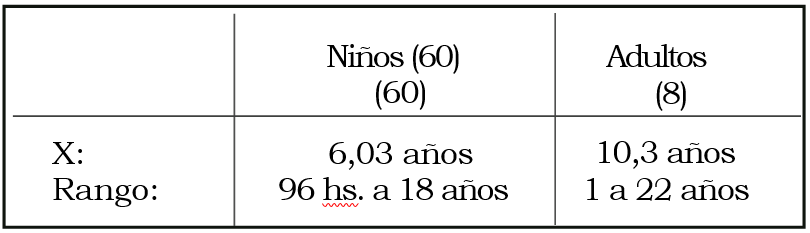

Entre junio de 1988 y abril de 2000 fueron operados por epilepsia refractaria 178 pacientes; de éllos 75 niños y 14 adultos padecían epilepsias extratemporales (EE). Se incluyen pacientes operados hasta junio de 1998, con un seguimiento no menor de 2 años. Se excluyen los pacientes a quienes se realizó callosotomía, con diagnóstico de síndrome de Lennox-Gastaud. La indicación de la cirugía en estos pacientes fue con criterio paliativo y dirigida especialmente al control de las caídas que padecían. En ellos no pueden aplicarse los criterios de Engel. (Tablas 1, 2 y 3).

Tabla 3. Tiempo de evolución de epilepsia

En un período de 12 años -1988-2000- fueron operados 178 pacientes por epilepsia refractaria (60 niños y 8 adultos), con un seguimiento postoperatorio mayor de 2 años. La edad media de los niños fue de 6 años, la de los adultos 30. La evolución media de las epilepsias hasta su tratamiento quirúrgico fue de 6 años en los niños y 10 en los adultos. Hubo un alto porcentaje de epilepsias sintomáticas (95,6%), acorde con lo comunicado por otros centros. Solamente 4/68 (5,8%) pacientes tuvieron epilepsias idiopáticas (criptogenéticas). De los 60 niños, 50 padecían epilepsias sintomáticas antes de los 10 años de edad, época a partir de la cual se puede considerar terminada la sinaptogénesis cerebral. Dilatar su tratamiento quirúrgico pudo haber llevado a que se perdiera la plasticidad neuronal y la posibilidad de recuperar funciones perdidas por la enfermedad misma o por eventuales déficits que pudieran agregar las cirugías a las que debieron ser sometidos8. En el 62,5% de los adultos las epilepsias comenzaron en edad temprana. Sin embargo, el desarrollo neurológico e intelectual fue normal. También la población adulta se benefició con la oportuna indicación de la cirugía. Mediante la IRM de alto campo desde 1997 se define el llamado protocolo para epilepsia que incluye cortes corona-les en FLAIR e I/R y cortes axiales a lo largo del eje mayor del hipocampo, especialmente útil en las epilepsias temporales. Mediante la IRM espectroscópica se efectuaron estudios volumétricos de los hipocampos. La IRM de alto campo en su modalidad de I/R fue fundamental para mejorar el diagnóstico preoperatorio de las epilepsias, incorporando a los diagnósticos diferenciales la llamada patología dual responsable del fracaso de cierto número de procedimientos quirúrgicos20-26.